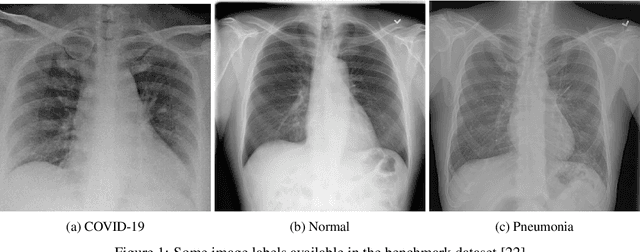

Abstract:This paper proposed an ensemble of deep convolutional neural networks (CNN) based on EfficientNet, named ECOVNet, to detect COVID-19 using a large chest X-ray data set. At first, the open-access large chest X-ray collection is augmented, and then ImageNet pre-trained weights for EfficientNet is transferred with some customized fine-tuning top layers that are trained, followed by an ensemble of model snapshots to classify chest X-rays corresponding to COVID-19, normal, and pneumonia. The predictions of the model snapshots, which are created during a single training, are combined through two ensemble strategies, i.e., hard ensemble and soft ensemble to ameliorate classification performance and generalization in the related task of classifying chest X-rays.

Abstract:The COVID-19 pandemic continues to severely undermine the prosperity of the global health system. To combat this pandemic, effective screening techniques for infected patients are indispensable. There is no doubt that the use of chest X-ray images for radiological assessment is one of the essential screening techniques. Some of the early studies revealed that the patient's chest X-ray images showed abnormalities, which is natural for patients infected with COVID-19. In this paper, we proposed a parallel-dilated convolutional neural network (CNN) based COVID-19 detection system from chest x-ray images, named as Parallel-Dilated COVIDNet (PDCOVIDNet). First, the publicly available chest X-ray collection fully preloaded and enhanced, and then classified by the proposed method. Differing convolution dilation rate in a parallel form demonstrates the proof-of-principle for using PDCOVIDNet to extract radiological features for COVID-19 detection. Accordingly, we have assisted our method with two visualization methods, which are specifically designed to increase understanding of the key components associated with COVID-19 infection. Both visualization methods compute gradients for a given image category related to feature maps of the last convolutional layer to create a class-discriminative region. In our experiment, we used a total of 2,905 chest X-ray images, comprising three cases (such as COVID-19, normal, and viral pneumonia), and empirical evaluations revealed that the proposed method extracted more significant features expeditiously related to the suspected disease. The experimental results demonstrate that our proposed method significantly improves performance metrics: accuracy, precision, recall, and F1 scores reach 96.58%, 96.58%, 96.59%, and 96.58%, respectively, which is comparable or enhanced compared with the state-of-the-art methods.